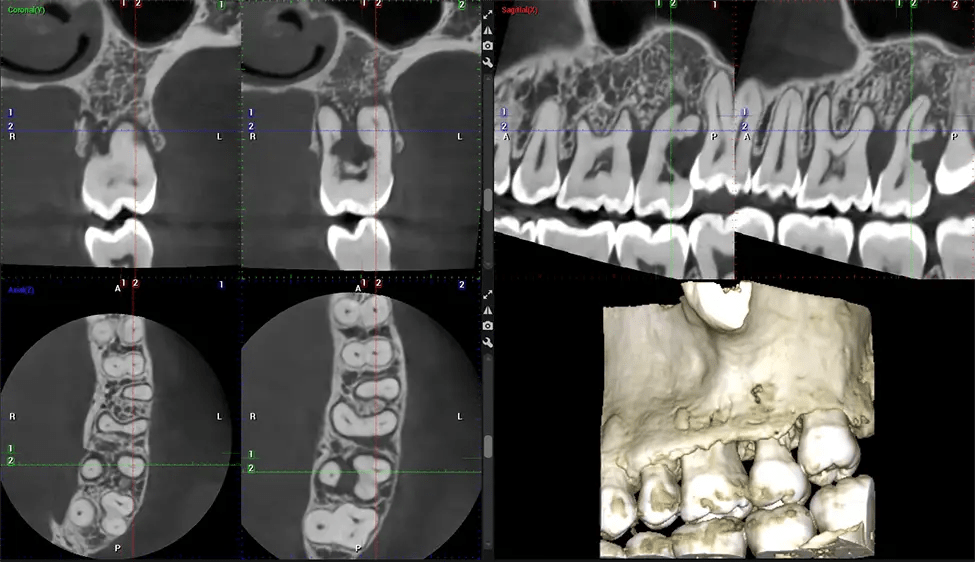

This 3D scan, called cone beam computed tomography, gives your dentist a more complete image of your oral anatomy and disease processes than a traditional X-ray. Unlike conventional X-rays, which capture a 2D image of your mouth from various angles, a 3D scan takes multiple digital X-rays for one image. It provides a complete view of your jaw, teeth, nerves, and soft tissues. This enhanced view allows dentists to detect minor issues not visible in traditional 2D scans, such as impacted wisdom teeth or bone fractures in the sinus cavity.

There are many benefits to using CBCT technology, especially compared to the traditional 2D X-ray format. One of the most significant advantages of CBCT scans is that they provide much more information than traditional X-rays. A scan lets your dentist see images from all angles of your jaw and mouth, including your sinuses, nasal cavity, cheekbones, and other surrounding areas. This added information helps your dentist craft a comprehensive treatment plan that addresses all aspects of your oral health.

Another significant benefit is that 3D imaging provides more precise images of your bone structure. These images are more detailed, providing you with a more accurate diagnosis. An accurate diagnosis means better treatment for you.

After the scanning process, the captured X-ray images are processed by the CBCT software, which applies algorithms to reconstruct a detailed 3D image of the scanned area. The software compiles these individual X-ray images and creates a digital 3D representation of the patient’s anatomy. The reconstructed 3D CBCT image can be viewed and analyzed by the dentist or radiologist. This image can be manipulated, rotated, and zoomed in or out to examine specific structures and evaluate the patient’s condition.

Our patented SCARA technology enables doctors to capture True Extraoral Bitewings that are as accurate at detecting caries as a 2D bitewing series, but with half the radiation dose. With our bitewings, doctors can view the apices of teeth on both jaws providing a more comprehensive view of the patients’ anatomy.